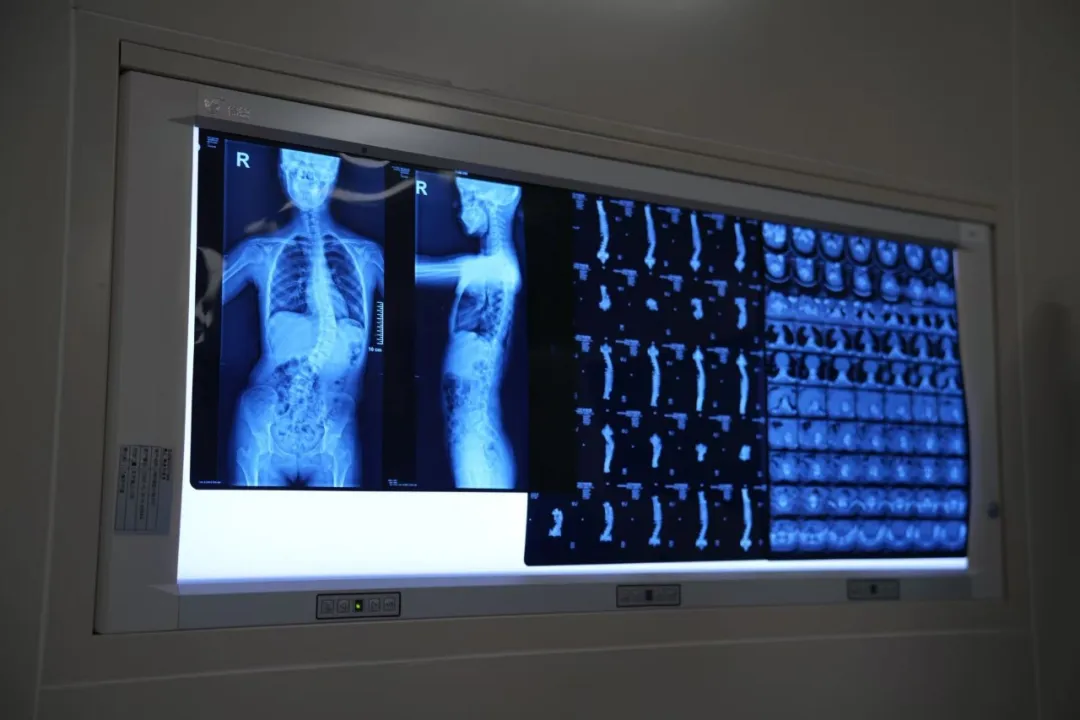

患者术前确诊脊柱侧弯8个月,脊柱呈S形畸形:胸椎左侧弯Cobb角约20°,腰椎右侧弯Cobb角约42°,伴有双肩不等高、胸廓不对称、肋骨突出等症状,已严重影响身心健康。

本次手术由国内脊柱畸形矫正领域专家梁益建教授主刀。循上鹏瑞利医院组建多学科(MDT)团队,涵盖脊柱外科、麻醉治疗中心、影像诊断中心、重症监护及手术室专科护理。

为保障手术实施,循上鹏瑞利医院专门配置了超声骨刀、血液自体回输装置及术中神经电生理监测系统,并在百级层流手术室环境中完成操作。术中实现骨组织精准切割、失血实时回收与回输、神经功能全程监测,用以降低异体输血与神经损伤风险。

在专家团队与MDT多学科协作下,本次手术全程耗时约5小时,优于同类手术通常所需的7-8小时。患者术中生命体征平稳,未出现明显神经、血管并发症,矫形效果达成术前预期。